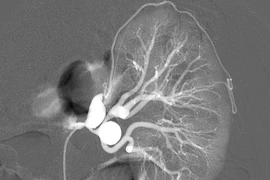

Bị đau lưng nhiều tháng âm ỉ, đau tăng dần nên anh N.V.M (Hà Nội) rất khó chịu. Cũng may là anh không sốt, không đái máu, không tiểu buốt, tiểu rắt nhưng vì trong gia đình có người bị viêm gan B nên anh vẫn cẩn thận đi khám.